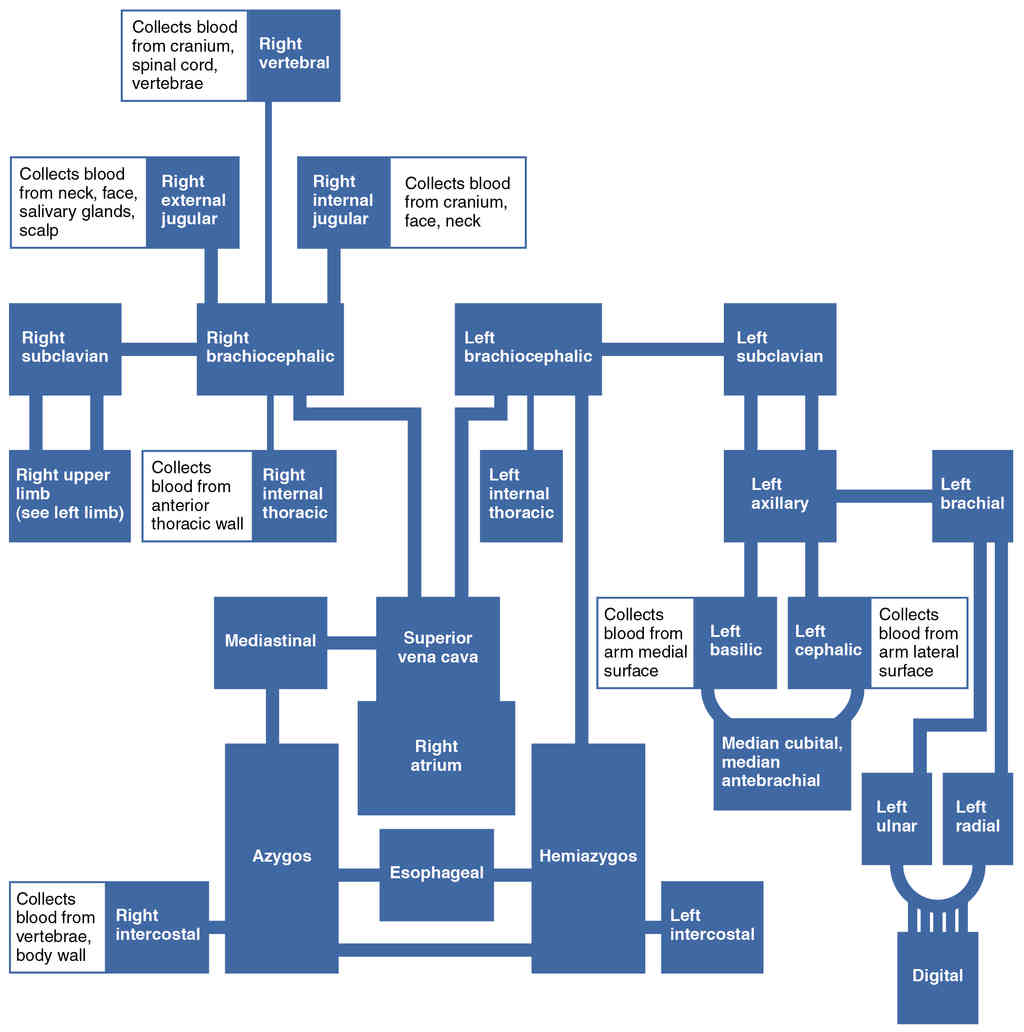

This page is under construction. For now, it is just a resource of the images found in the OpenStax Anatomy and Physiology Handbook. It wil slowly change into a revision tool. Each slide has a number. Use this to refer to the slide. When completed, it will have an unlabelled section, with labelled slides in parallel. On the unlabelled slides, write your answer and use the labelled slide to assess yourself. Keep track by also noting the number on each slide. Improvement at each attempt is important, more so than full marks on a first attempt.